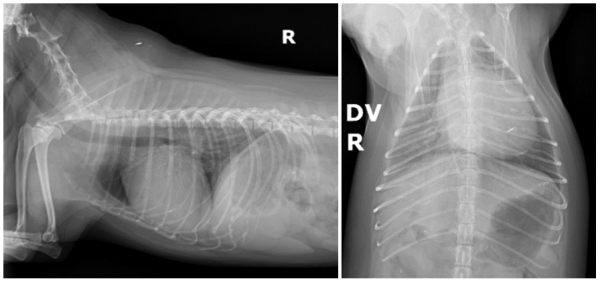

즉각적인 원인 평가를 위해

흉부 영상검사를 진행했습니다.

영상검사에서 확인된 폐와 심장의 변화

흉부 방사선 검사 결과

로또의 심장과 폐에서 중요한 변화가 확인되었습니다.

검사 결과

-심비대 (VHS 12.8)

-좌심방 및 폐정맥 확장

-우측 폐엽 간질 침윤

이러한 소견은 심인성 폐수종(CPE)이

가장 의심되는 상황이었습니다.

다만 증상이 갑작스럽게 발생한 점,

영상 소견에 비해 극심한 호흡곤란을 보인 점을 고려하여

비심인성 폐수종(NCPE) 가능성도 함께 평가하며

치료를 진행하기로 결정했습니다.